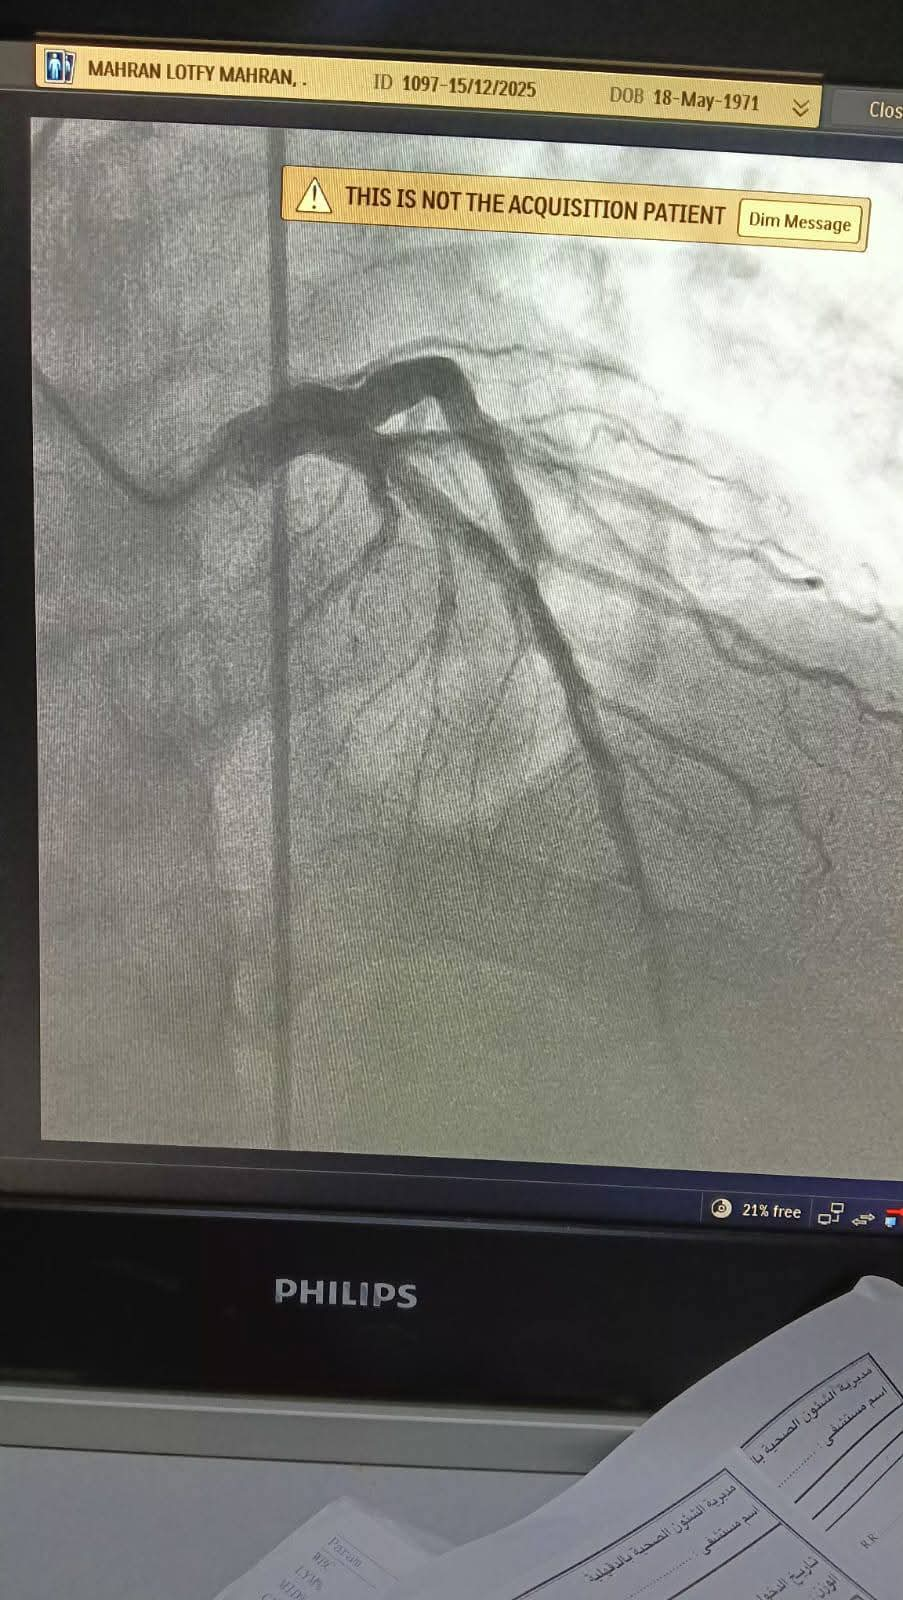

وبمجرد وصول المريضة إلى مستشفى ميت غمر العام عن طريق الإسعاف، تم إجراء الفحوصات والتحاليل اللازمة بشكل عاجل، وتجهيزها للتدخل الطبي، حيث جرى إدخالها لإجراء قسطرة قلبية تشخيصية خلال وقت قياسي، كشفت عن وجود جلطة بالشريان التاجي أثرت على تدفق الدم إلى عضلة القلب.

وعلى الفور، تم التعامل مع الحالة وإزالة الجلطة بنجاح، مما أدى إلى تحسن سريان الدم واستقرار الحالة الصحية للمريضة، وتم نقلها إلى العناية القلبية لاستكمال العلاج والمتابعة حتى خروجها بحالة جيدة.